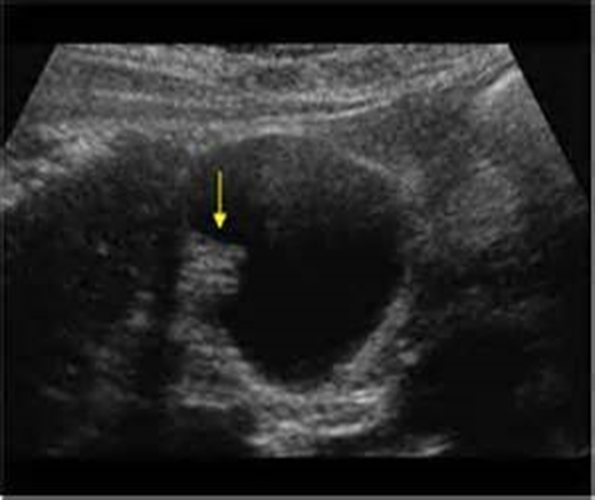

What is being shown in this image above?

Metastases to Biliary Tree

What is being shown in this image above?

Biliary Tree metastases